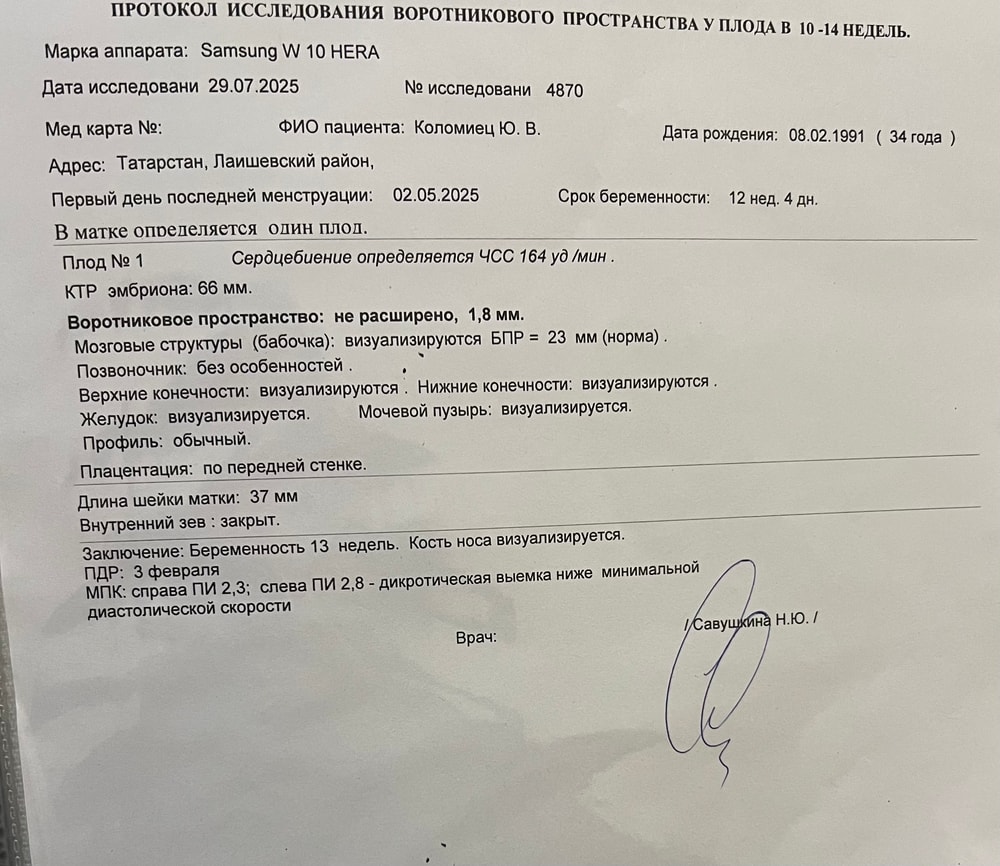

Не понравились кровотоки, усилили терапию с гематологом, через 2 недели контроль узи. А кнопки тьфу тьфу хорошо🙏🙏🙏растёт❤️сейчас напишу пост в дневник

Не понравились кровотоки, усилили терапию с гематологом, через 2 недели контроль узи. А кнопки тьфу тьфу хорошо🙏🙏🙏растёт❤️сейчас напишу пост в дневник